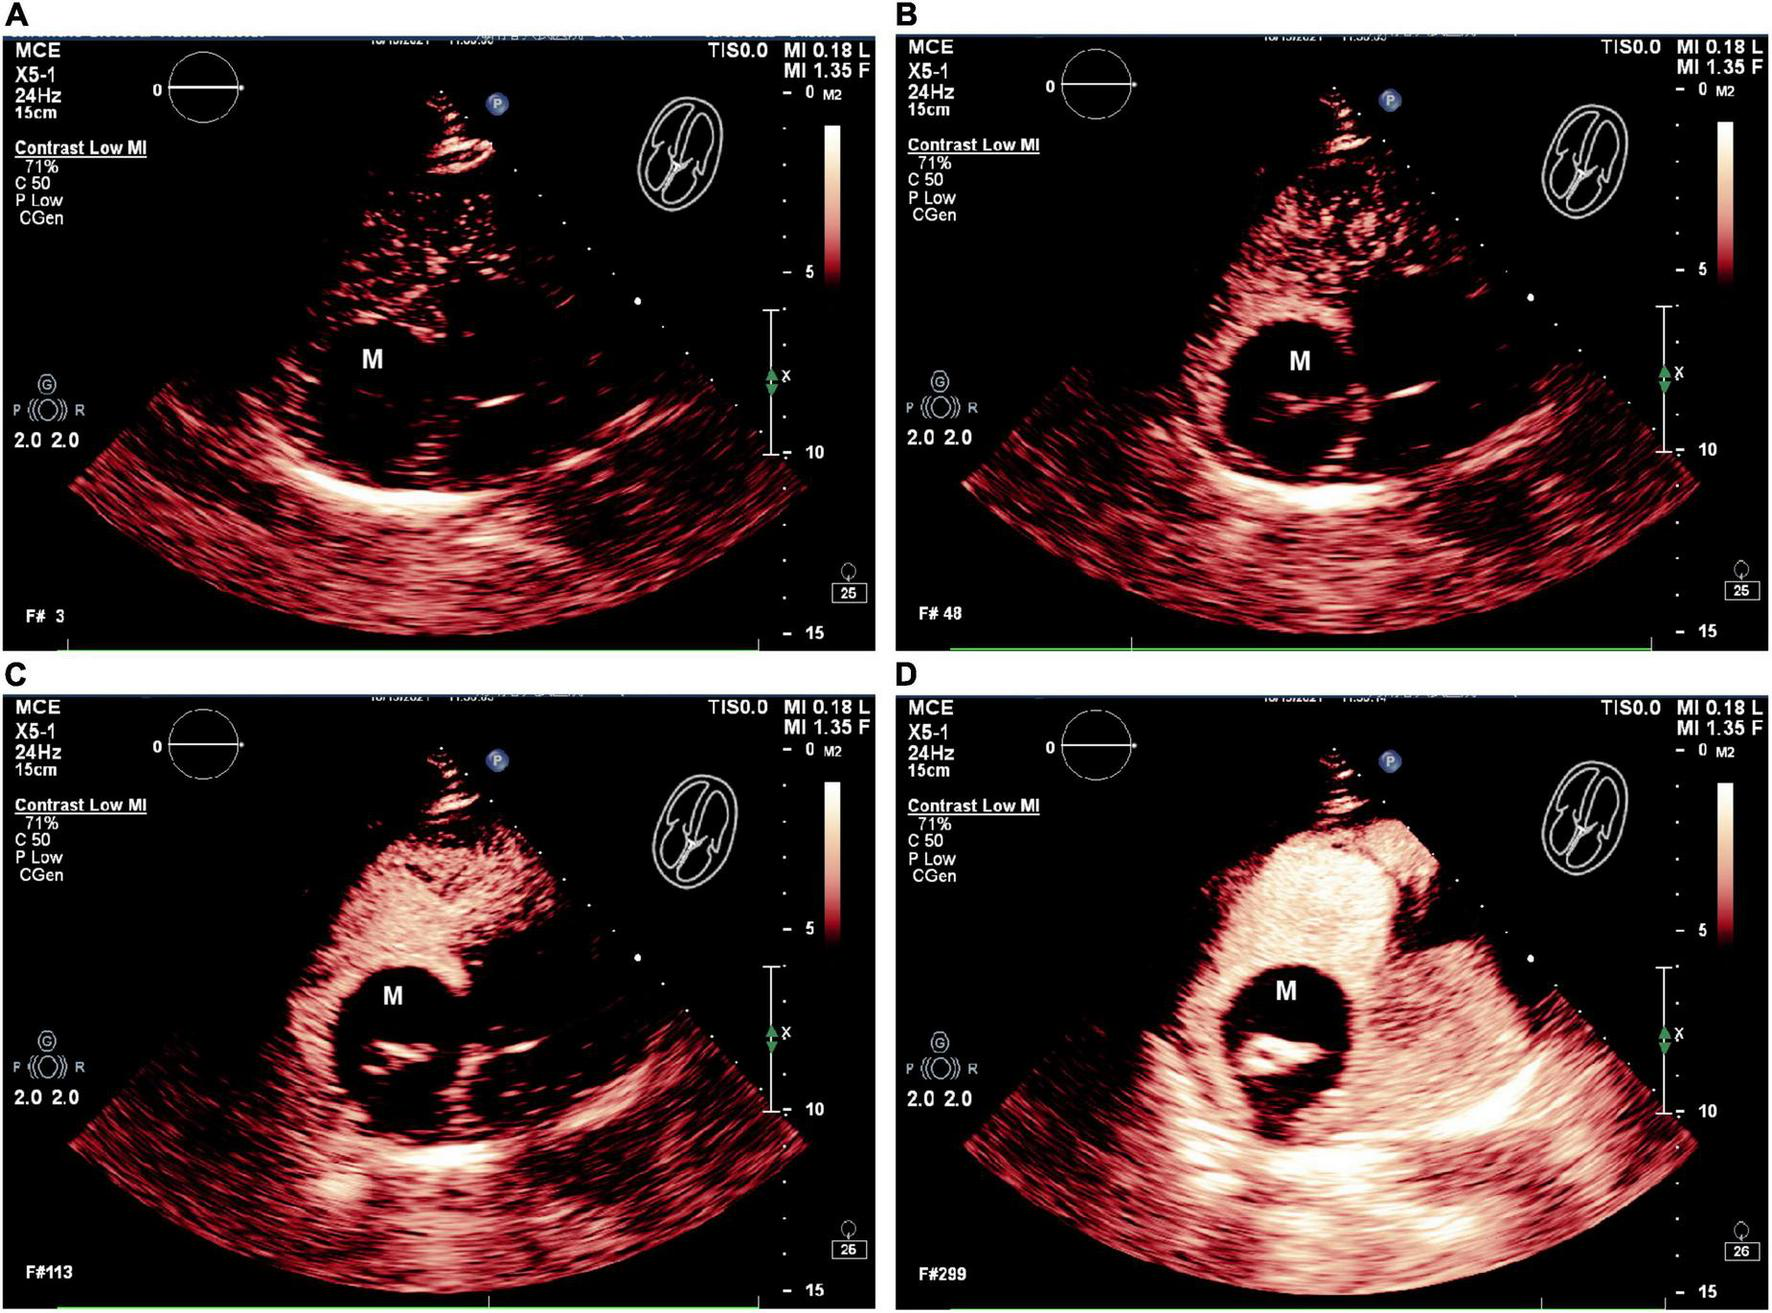

Two-dimensional transthoracic echocardiography (2D-TTE, Philips EPIQ CVx-Philips Medical Systems, Andover, MA, USA) revealed mild dilatation of the right atrium, with a predominantly cystic-solid mixed echogenic lesion that was present the right atrium with a rounded shape and a pedicle attached to the right atrium (Figures 1A, B). The atrial septum measured approximately 40 mm × 44 mm proximal to the fossa ovalis on the side of the right atrium, and significant echoic enhancement was observed for the solid portion of this mass (about 30 mm × 15 mm in size). No apparent obstruction or hemodynamic abnormalities were observed in the Valvular orifice (Figure 1C). No obvious abnormalities were apparent upon sonogram-based examination of the inferior vena cava (Figure 1D). Echocardiography confirmed the presence of a right atrial cystic solid mixed echogenic space-occupying lesion of uncertain etiology that was primarily cystic, with significantly enhanced echoic signal in the solid regions.

FIGURE 1

www.frontiersin.org

Figure 1. Echocardiography showed a large cystic-solid mixed echogenic lesion in the right atrium. Apical four-chamberview (A) and subxiphoid four-chamber view (B) showed that the mass was attached to the right atrial surface of the atrial septum. Ultrasound findings of tricuspid valve orifice (C) andinferior vena cava (D). M = (intracardiac mass).

The patient next underwent contrast-enhanced ultrasonography (Philips EPIQ CVx-Philips Medical Systems, Andover, MA, USA). After initiating the intracardiac contrast mode, the depth, gain, and instrument frame rate were adjusted such that the target lesions were clearly visible, after which the mechanical index (MI) was set to 1.0. Then, using SonoVue (Bracco, Italy) as an acoustic contrast agent, 5 mL of 0.9% sodium chloride was mixed with SonoVue microbubbles, and 2.4 mL of this mixture was gradually injected via the patient’s left cubital vein to observe the filling of the cardiac cavity, the lesion site, and myocardial tissue contrast-enhanced performance. The resultant dynamic image was stored for analysis. CEUS results revealed high contrast enhancement in the solid echoic mass in the center of the right atrial tumor, while no contrast enhancement was evident in the surrounding anechoic area (Figure 2). No abnormal contrast enhancement was observed in the other cardiac chambers or the myocardium. Accordingly, this right atrial cystic-solid mixed space-occupying lesion was tentatively diagnosed as a potential cardiac teratoma.

FIGURE 2

Figure 2. The RA mass was seen on contrast enhancement ultrasound (CEUS). (A–D) CEUS results showed that in different cardiac cycles, which the solid echo mass in the right atrium tumor revealed high contrast enhancement, and no contrast enhancement is evident in the surrounding anechoic area. M = (intracardiac mass).